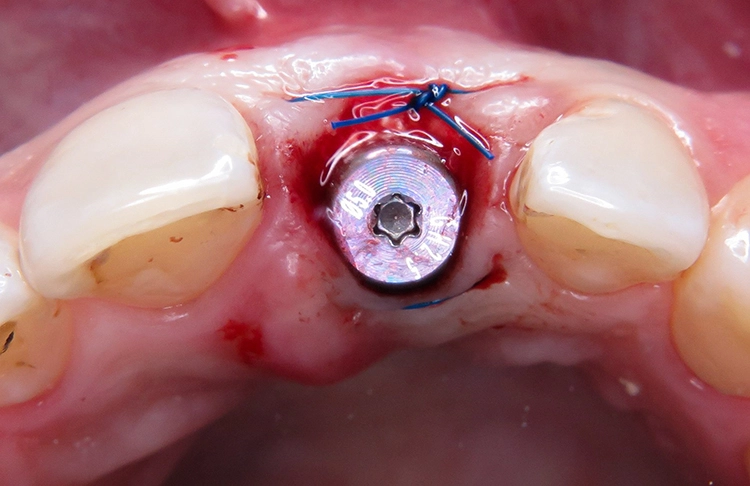

Unter Lokalanästhesie wurde der beherdete Zahn 21 extrahiert und hierbei auf die maximale Schonung der vestibulären Lamelle geachtet. Die Entzündung konnte rückstandslos entfernt werden. Die Sondierung ergab eine intakte faziale Knochenlamelle (Abb. 6). Die frische Extraktionsalveole wurde als Implantatbett aufbereitet und das Implantat (BLX ø 4 mm, 14 mm) entsprechend der Planung dreidimensional im palatinalen Bereich der Alveole inseriert [3,6] (Abb. 7 und 8).

Das BLX-Implantat hat einige Besonderheiten im Design. So nimmt beispielsweise das Gewinde des Implantats zum krestalen Bereich hin an Stärke zu, sodass zusätzlich zur horizontalen Kondensation auch vertikal Knochen kondensiert wird. Ziel ist eine Primärstabilität im gesamten Implantatbett basierend auf einer homogenen Krafteinleitung. Drucknekrosen sollen so verhindert werden. Im krestalen Bereich ist das Implantat um 1/10 reduziert, um das sensible Gewebe in der Kortikalis drucklos zu lassen. Das BLX-Implantat konnte mit einer für die Sofortversorgung ausreichenden Primärstabilität (mind. 45 N/cm2) inseriert werden.